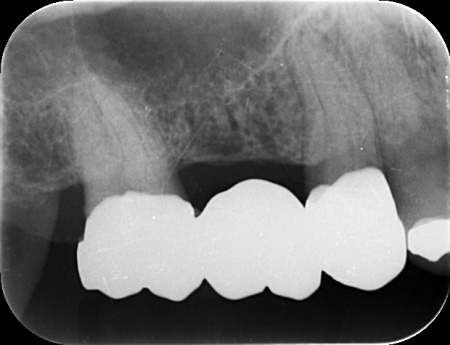

| カウンセリング | 拝見したところ、右上の奥歯には複数の歯をつないだ被せ物であるブリッジが入っていましたが、被せ物の内部で虫歯が再発していました。 レントゲンを撮影して詳しく調べた結果、虫歯は比較的大きく歯の神経に近い深さまで進行していることが確認できました。 このまま放置すると、神経に炎症が起こって強い痛みが出る、神経が死んでしまい歯を温存できなくなるといった可能性があります。 以上のことから、ブリッジを取り外して虫歯を治療する必要があると診断しました。 |

①MTA歯髄温存療法(神経を残す治療) ②根管治療(神経を取る治療) 患者様は「歯を長持ちさせたい」との希望から、①MTA歯髄温存療法を選択されました。 まずブリッジを慎重に取り外し、虫歯を確認します。 数週間後、しみたり痛んだりする症状は認められず、コールドテストとバイタルテストでも歯の神経が問題なく機能している状態であると判断できました。 神経が温存できていることを確認できたため精密な型取りを行い、虫歯の再発リスクが低く強度も高いセラミックのジルコニアでブリッジを新たに作製しました。 |